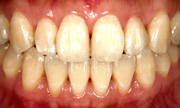

【施術前】

【施術後】

※上の写真は、ジェットポリッシャー使用前後のものです。

痛みも無く、白い歯を手に入れることが出来ます。